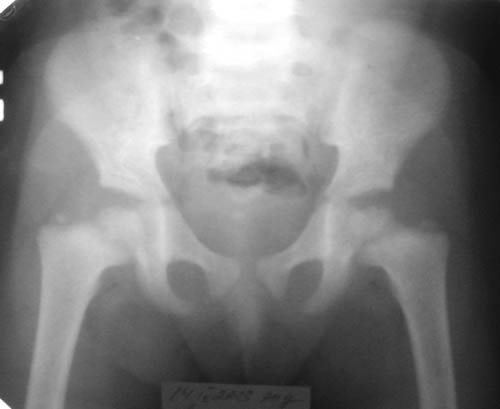

ТазКистиГолени

Девочка, 3 года 11 мес. Дз: Фосфатдиабет (витамин Д-резистентный рахит).

Жалобы на задержку роста. Общие анализы крови и мочи без особенностей.Биохимический анализ крови: билирубин 7,7, АЛТ 0,30, общий белок 73, креатин 0,061, щелочная фосфотаза 49%мл/г, K+ 4,4, Na+ 139, Ca++ 0,93, Ca общий 2,5.УЗИ органов брюшной полости: норма, печень увеличена, паренхима однородна, сосудистый рисунок сохранен. Рентгенологический возраст 2 года, хронологический возраст 4 года. Ранее рекомендована ЛФК, витамины, видеин.Рекомендации по лечению? Заранее благодарен! С уважением, А.В.Владзимирский Донецкий НИИ травматологии и ортопедии